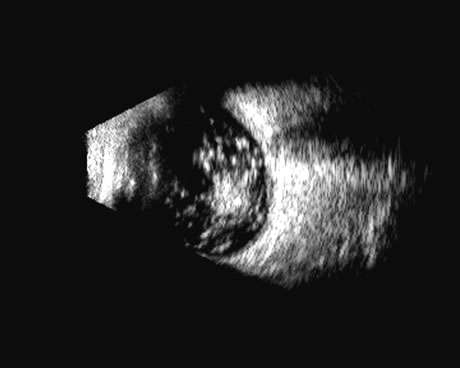

Two-dimensional scans through complex three-dimensional structures, such as preretinal membranes and proliferative membranes, can be confusing unless mapped with three-dimensional conceptualization techniques. Bronson and colleagues15 have emphasized three-dimensional thinking. Although new digital three-dimensional ultrasound systems allow direct volume visualization, it remains useful to understand the technique of conceptualizing three-dimensional structures from individual sections.16 Preretinal membranes (Fig. 15), which may resemble traction detachments in thickness and reflectivity, can often be identified by turning the scan plane of the B-scanner at right angles: the disciform retinal elevation is still seen while the linear nature of a traction sheet is revealed.17 A three-dimensional rendering of a retinal detachment can directly show the conformation of three-dimensional structures (Fig. 16), and images of individual planes can be perceived.

Fig. 15. A preretinal membrane is attached to the retina, producing a traction retinal detachment. A single-scan plane is often confusing: serial scans and movement of the patient's eye (kinetic scan) are required to conceptualize the vitreoretinal anatomic relationships. Computer reconstruction provides a significant advance in this area for ease of interpretation.

Fig. 16. 3D depiction of a retinal detachment can be helpful in situations in which there is ambiguity among retina, choroid, and schisis. The 3D rotatable display can be perceived from different perspectives, often aiding in the certainty of diagnosis.